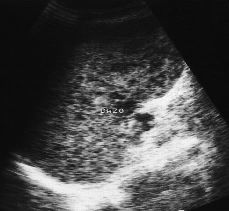

Abdomen La ecografía abdominal en los pacientes con sida

Abdomen Abdominal ultrasound in AIDS patients